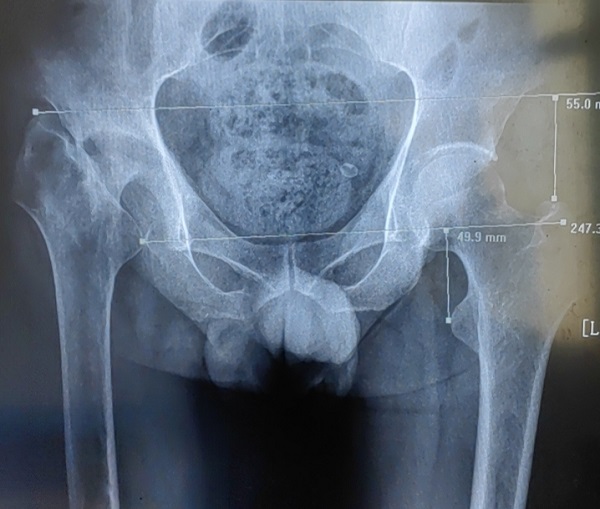

股骨頭壞死的原因多種多樣,其中最被公認的是髖關節(jié)骨折創(chuàng)傷后骨不連及股骨頭壞死。一旦發(fā)生壞死,幾乎為不可逆性發(fā)展,發(fā)展到一定程度將嚴重影響患者工作和生活。 李師傅今年54歲,11年前因外傷致股骨頸骨折在外院...